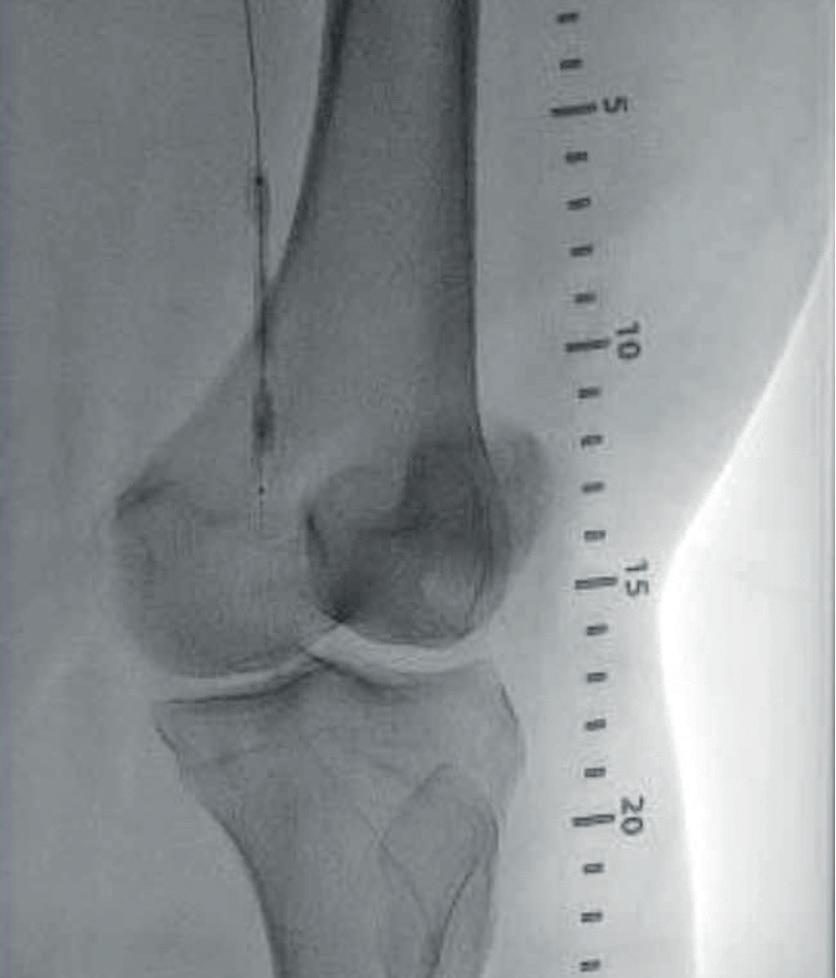

SEE OUR APPROACH When you reach for a balloon expandable covered stent, you require placement accuracy. The LifeStream™ Expandable Vascular Covered Stent was developed for the challenging anatomy and engineered to facilitate accurate placement Dr. Ray Norby shows a kissing stent procedure featuring the advantage of the 6F LifeStream™ Balloon Expandable Vascular Covered Stent in a patient who could not tolerate a 7F sheath. Initial Angio Kissing Stents Placed Result The LifeStream™ Balloon Expandable Vascular Covered Stent is indicated for the treatment of atheroslerotic lesions in common and external iliac arteries with reference vessel diameters between 4.5 mm and 12.0 mm, and lesion lengths up to 100 mm. Not for use in patients with uncorrected bleeding disorders, who receive recommended antiplatelet and/or anticoagulation therapy, or who are judged to have a lesion that prevents full expansion of the implant. Please consult product labels and instructions for use for indications, contraindications, hazards, warnings and precautions. BD, the BD Logo, and LifeStream are trademarks of Becton, Dickinson and Company or its affiliates. © 2023 BD. All rights reserved. © 2023 Illustration by Mike Austin. BD-86589 bd.com BD, Tempe, AZ, USA, 1 800 321 4254

ACCURACY Images courtesy of Dr. Norby.

DESIGNED TO DELIVER PLACEMENT